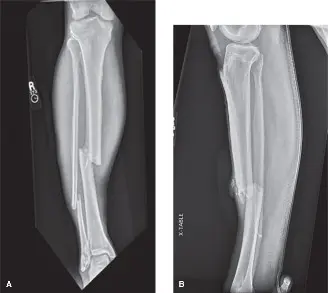

• الأشعة السينية (X-rays): تُجرى دائمًا لتقييم وجود كسور عظمية أو خلع، والتي غالبًا ما تكون السبب الكامن وراء متلازمة الحيز. في حالة السيد "ج.د."، أظهرت الأشعة السينية كسرًا حلزونيًا في منتصف عظم الساق.

• تثبيت الكسر: في حالة كسر عظم الساق (كما في حالة السيد "ج.د.")،